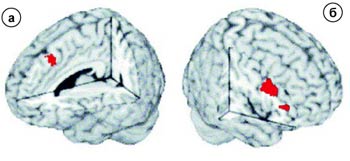

Величина магнитно-резонансного сигнала зависит от того, в какой степени гемоглобин насыщен кислородом. А величина кровотока (то есть уровень кислорода) в определенной зоне мозга определяется ее работой (функциональной активностью). Поэтому исследователь может регистрировать степень насыщения крови кислородом, отражающую включение в работу той или иной зоны мозга, - результат возбуждения коры в ответ на разные виды стимуляции (чередование фаз двигательной, мыслительной или иной активности пациента и покоя). Этот метод позволяет изучать деятельность различных отделов мозга, строить их карты, в том числе карты моторной, сенсорной коры, зон речи и слуха. Сопоставление карт активации и стандартных томограмм (в покое) исследуемой области позволяет провести параллели между отдельными функциями. Именно так было достоверно установлено, что музыка возбуждает области мозга, связанные с эмоциональным поведением, такими, как островок мозга, гипоталамус, гиппокамп, миндалина и префронтальная кора. Оказалось, что музыка радости усиливает кровоток в вентральной и дорсальной областях полосатого тела, передней поясной извилине, парагиппокампальной извилине и области слухового восприятия. В то же время печальная музыка возбуждает гиппокамп (миндалину) и область слухового восприятия. В ответ на воздействие нейтральной музыки наблюдалось активирование островка мозга и области слухового восприятия.